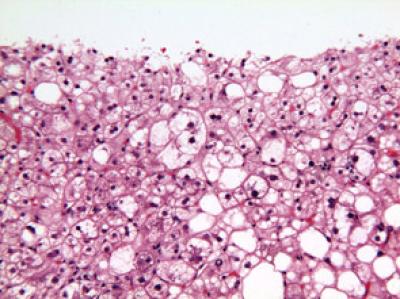

The second shows nonalcoholic steatohepatitis (NASH), a more serious condition with potential to progress to cirrhosis.

Elizabeth Brunt, M.D., of Washington University in Saint Louis.